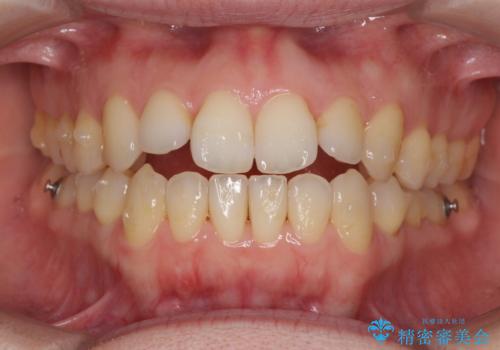

前歯の叢生とオープンバイト インビザラインでの矯正治療

- 前歯の開咬を気にして来院された患者様です。

開咬の治療は、前歯を閉じるように動かすとともに、上下臼歯を圧下(骨内にめり込ませる)させることで進めて行きます。

インビザラインは臼歯の圧下を効果的に行えるため、インビザラインを用いて矯正治療を行うこととしました。